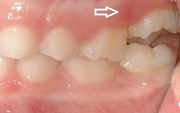

kaaries igemeäärel

kaaries